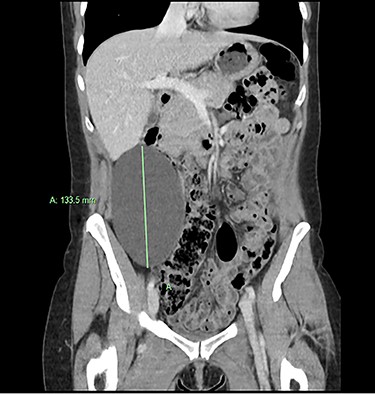

We present an extremely rare and isolated case of primary mixed serous and mucinous cystadenoma in a 49-year-old otherwise fit and healthy female patient. She was referred to our consultant with a history of discomfort on the right side of her abdomen for few years, which increased gradually with no other complains. The patient had further investigations conducted including computed tomography (CT) (Figs 1 and 2) that demonstrated the position and size of the lesion. The magnetic resonance imaging (MRI) revealed a large cystic lesion in the right retroperitoneal region shown in Figs 3 and 4. Her full blood count, inflammatory markers, urea and electrolytes and liver function tests were within the normal limit. Consequently, the patient had a laparoscopic resection of an isolated retroperitoneal cyst. At surgery, the cystic lesion seemed to be arising from mesentery and the lesion was dissected intact and completely excised. Histopathology revealed a benign mixed serous and mucinous cystadenoma as shown in Fig. 5. The patient was discharged from the hospital with no complications and fully recovered on follow-up review. Patient was discussed in a multidisciplinary team meeting and the recommendation was for no further management.